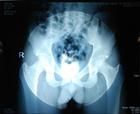

先天不足,性別相傳,機能減退,四肢百骸溫煦滋長匱乏,衛外不固,生化乏源,筋骨萎軟,未老先衰,齒牙乏脫,壽未終命先夭為大僂病之理。在X光片顯示下,骶髂溝有線條狀浮生物,髖外臼增厚,四肢百骸骨上軟骨變薄,椎體周圍韌帶退化,病程日久在X光顯示下退化日重。